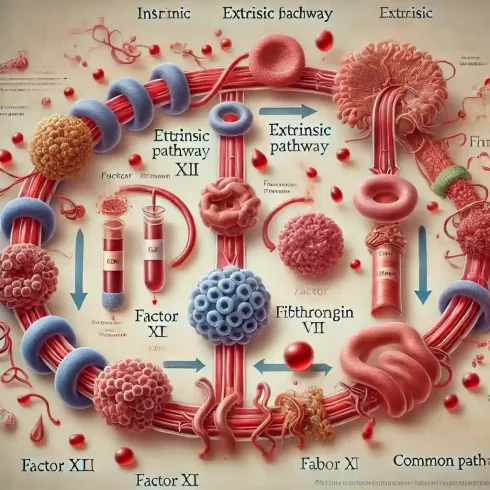

مسیرهای انعقادی خون و آزمایشات مرتبط با آن

مقدمهای بر مسیرهای انعقادی خون فرآیند انعقاد خون یکی از مهمترین مکانیسمهای دفاعی بدن است[بیشتر بخوانید]